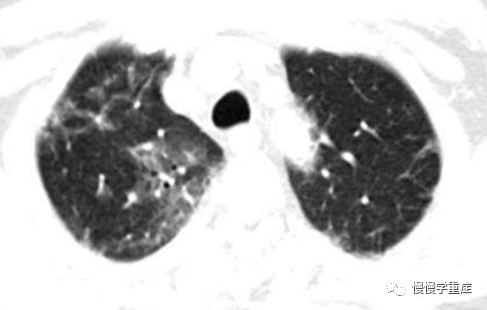

PCP会出现肺间质损害为主的渗出性毛玻璃状影和渗出性斑片状影,肺泡中低密度的泡沫样渗出物及弥漫性肺泡间质炎症是PCP患者胸部影像学呈弥漫性毛玻璃样改变的病理学基础,严重者可见斑片状影;病灶由肺门区向肺野辐射发展,但肺尖或上肺野清晰。X 线透视早期并无显著症状,而随着病情进展,可见肺门弥漫性间质性浸润,自肺门向肺野扩散,进而累及整个肺实质,严重者可以出现气胸。据调查,35%患者出现渗出性毛玻璃影,病灶自肺门向肺野辐射发展;29%为渗出性斑片状影,病灶大小不一、边界不清;还有的表现为间质性实变影;气囊性病变指的是肺内或胸膜多个大小不一的圆形,对称或多发性,直径1-6cm,囊内无内容,内外壁光滑。很少病人会出现粟粒样改变,两肺野或大部分肺野布满粟粒状、 大小不等的结节状、 小片状、 粗细不等的线条或网格状、 蜂窝状阴影。

图示:两肺不对称的渗出性病变 , 左肺有多个大小不等的囊肿